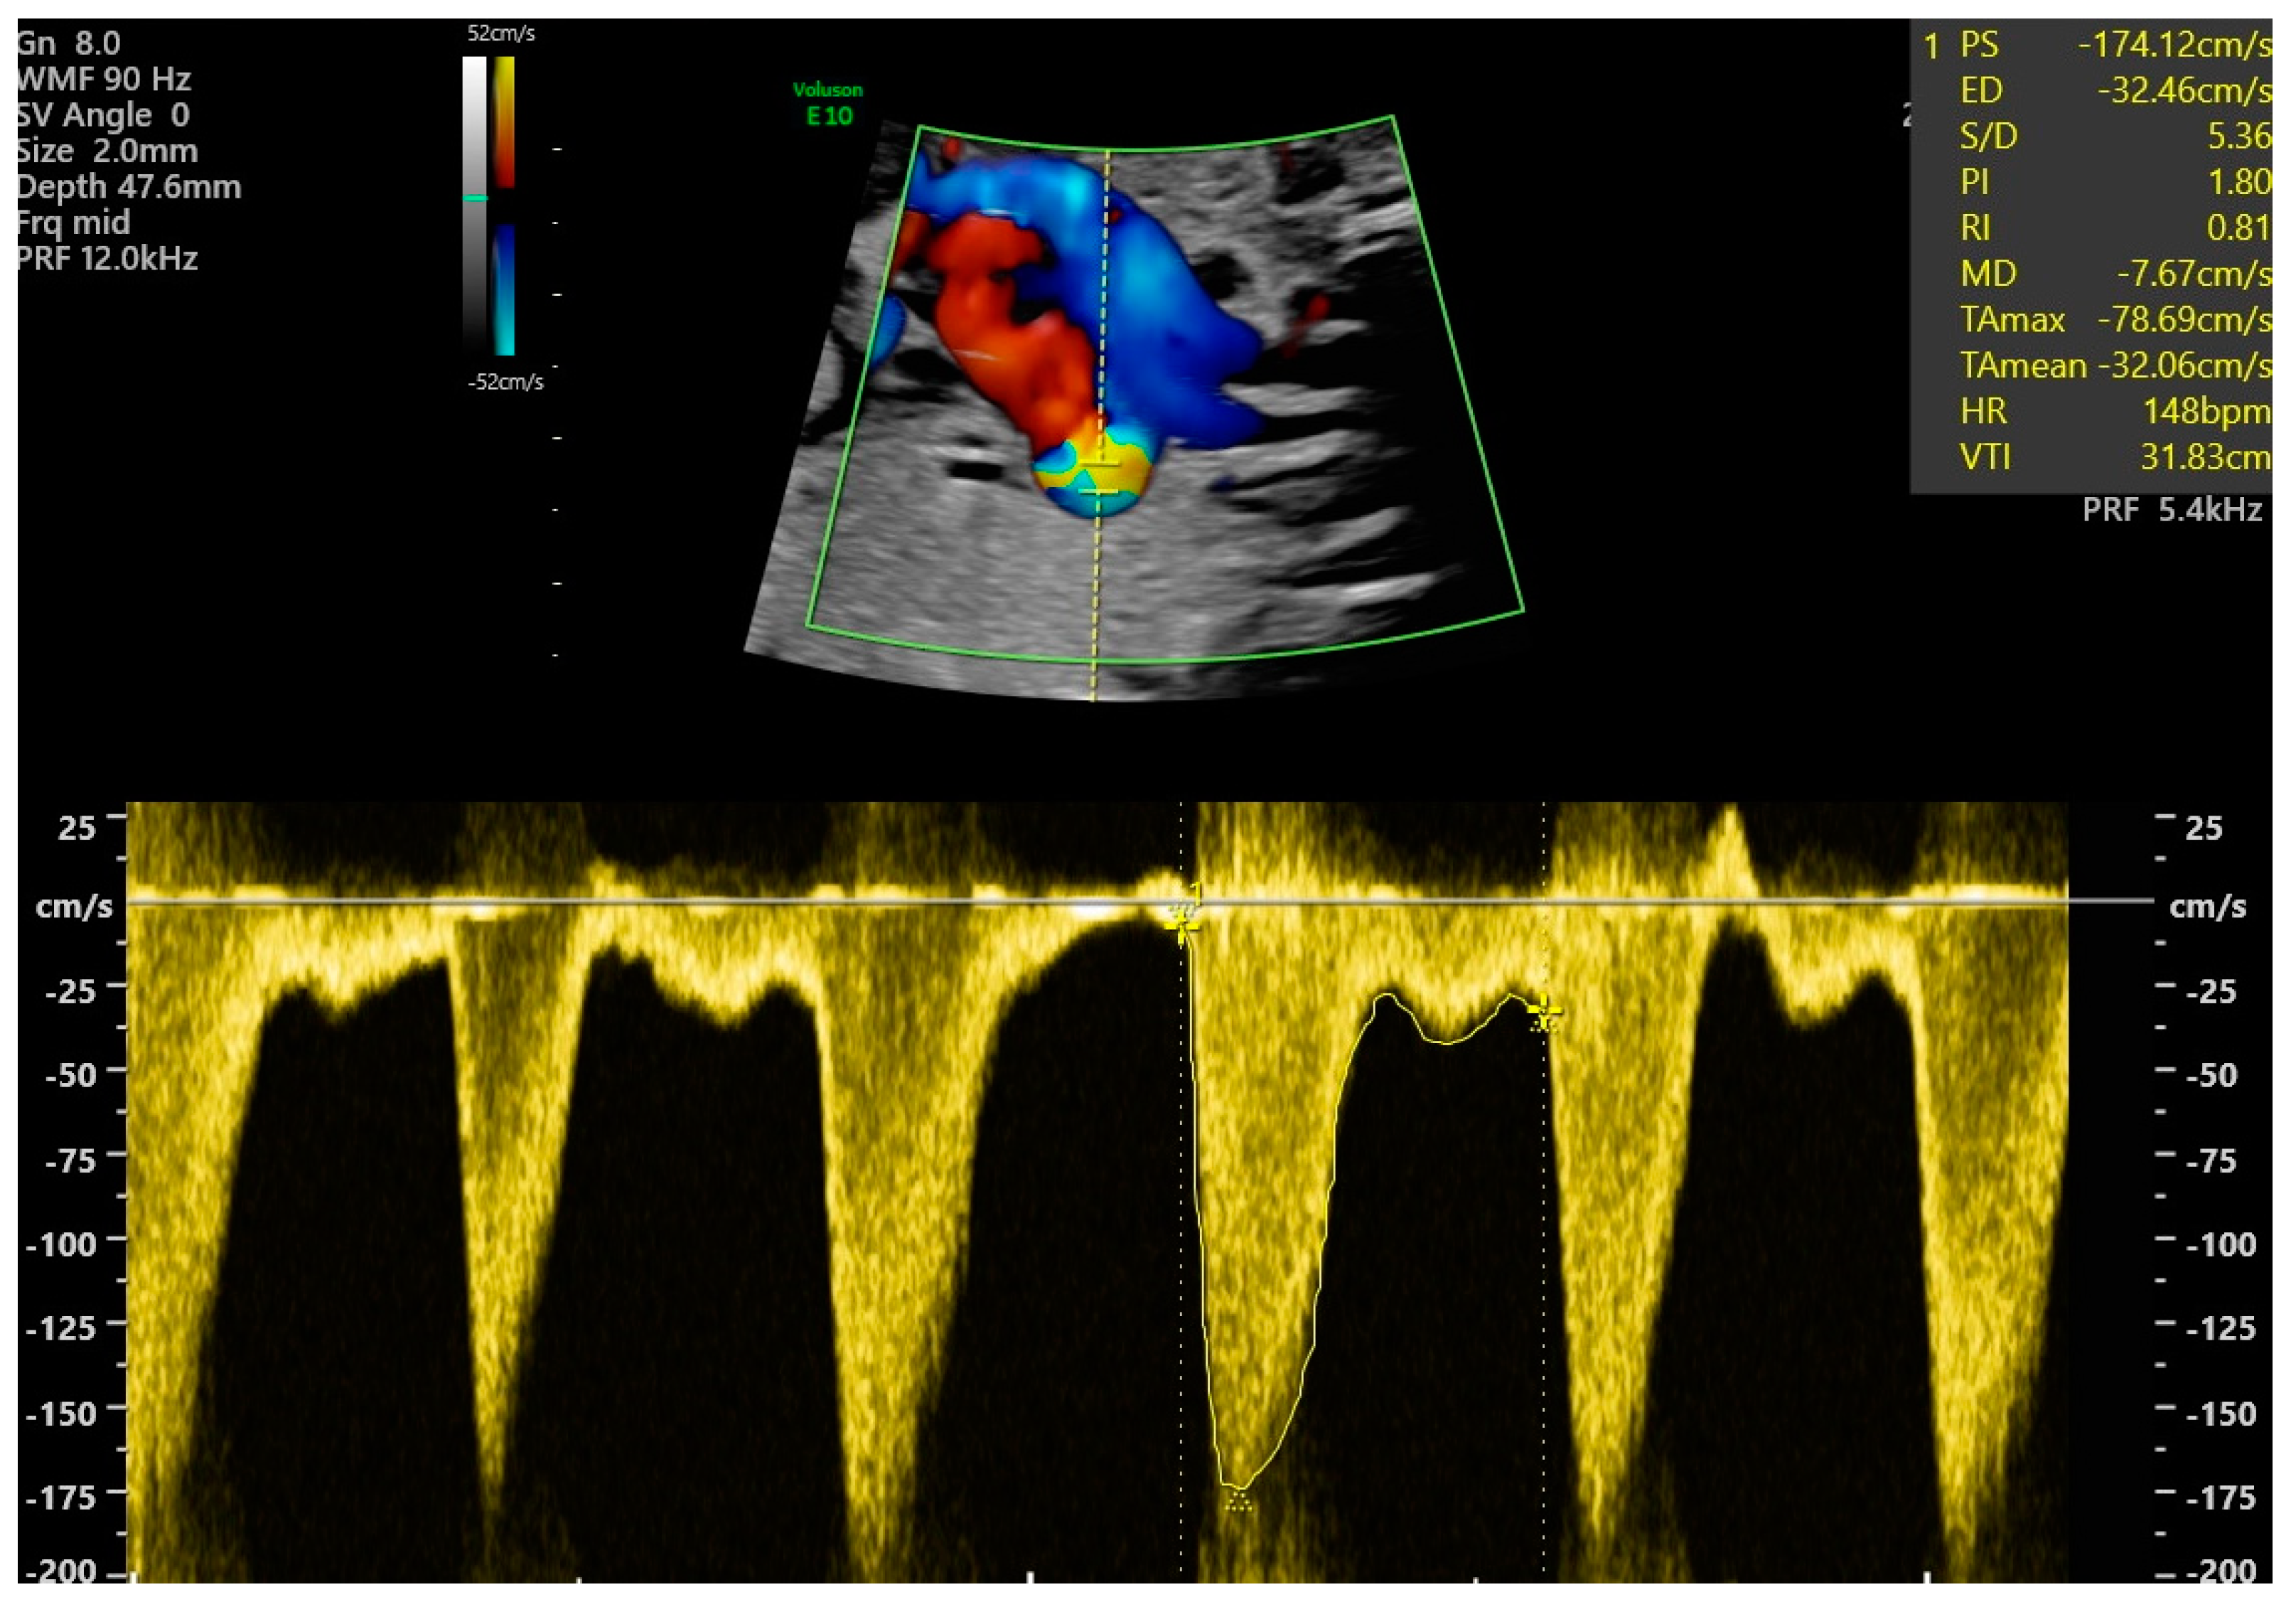

| PSV | Peak systolic velocity |

| PI | Pulsility index |

| PDV | Peak diastolic velocity |